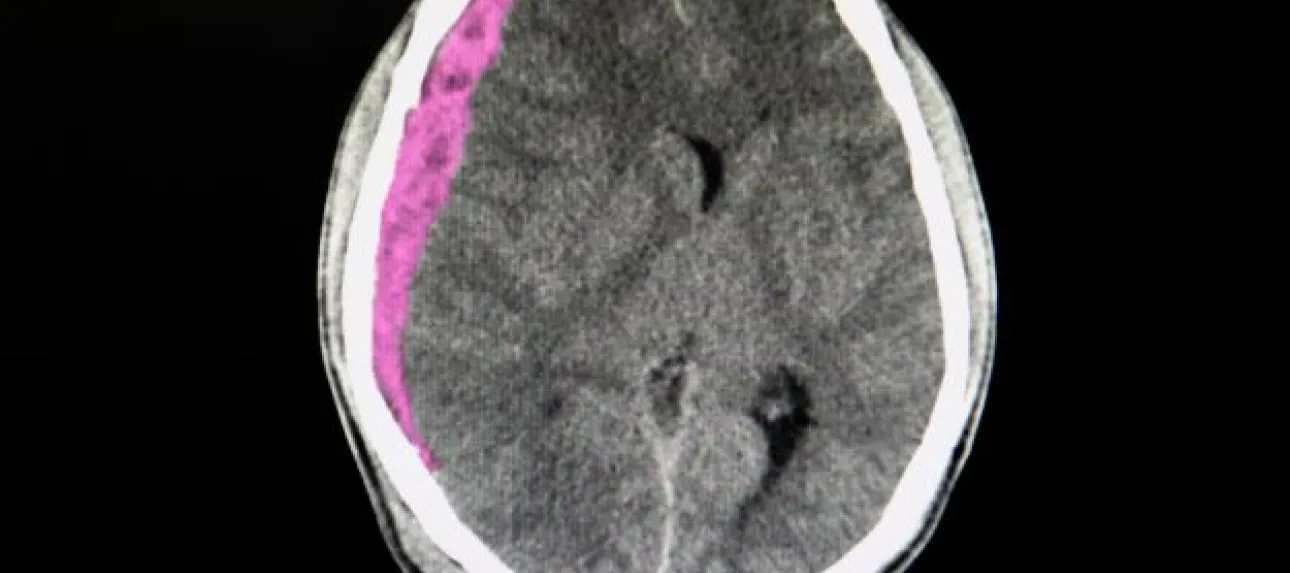

hématome sous dural

L'hématome sous-dural représente la complication la plus fréquente et la plus redoutable chez les seniors. Cette accumulation de sang entre le cerveau et la dure-mère peut se développer lentement, sur plusieurs jours ou semaines. Chez les personnes âgées, même un choc mineur peut provoquer cette lésion en raison de la fragilité accrue des vaisseaux sanguins et de l'atrophie cérébrale naturelle qui crée un espace plus important dans la boîte crânienne. Les symptômes peuvent inclure des maux de tête persistants, une somnolence progressive, des troubles de la mémoire ou des changements de comportement.